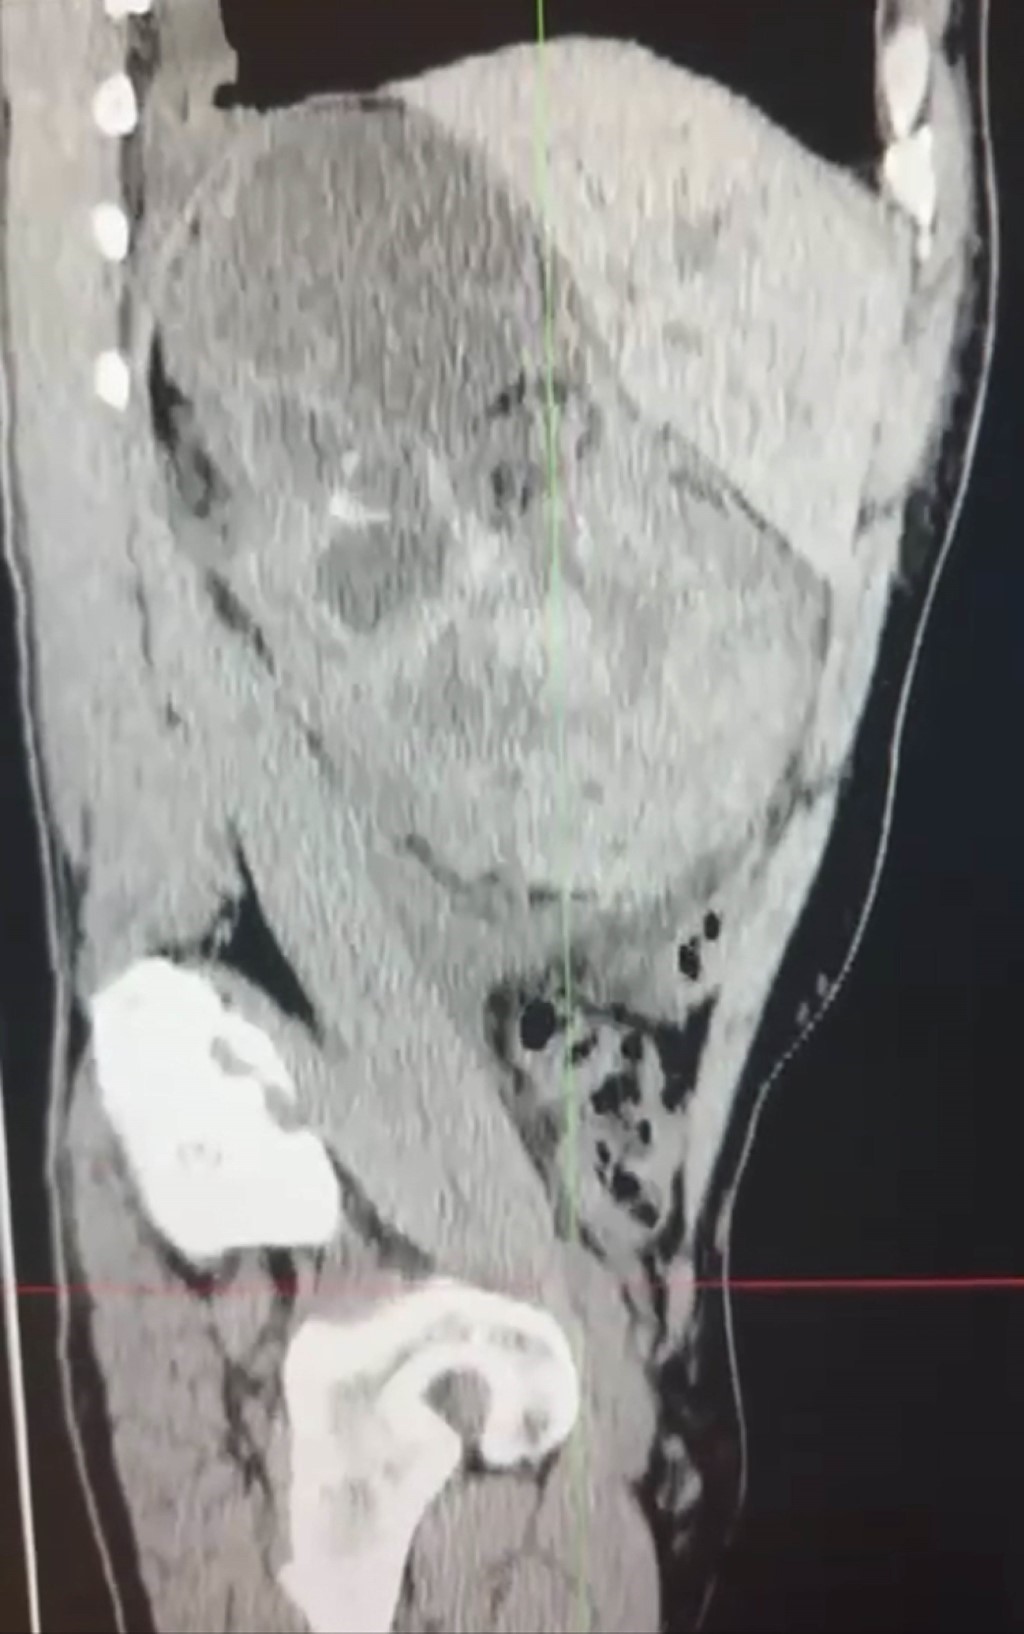

Paciente masculino de 52 años con antecedente de tuberculosis genitourinaria, actualmente inactiva con secuelas anatómicas en vías urinarias inferiores. Se presenta con dolor de inicio súbito localizado en flanco derecho, irradiado hacia fosa iliaca ipsilateral, acompañado de hematuria de aproximadamente de seis horas de inicio. A la exploración física se observa abdomen irregular por aumento de volumen en flanco e hipocondrio derechos, con hipersensibilidad a la palpación en región anteriormente mencionada. Biometría hemática (BH) con hemoglobina de 8 g/dL. Se encuentra actualmente en protocolo para trasplante renal debido a enfermedad renal terminal secundaria a las secuelas por tuberculosis. Se realiza tomografía axial computarizada (TAC) simple abdomino-pélvica, donde es evidente una colección perirrenal derecha de gran tamaño que se extiende por retroperitoneo hasta fosa iliaca ipsilateral (Figuras 1 y 2). Posteriormente, en nueva BH de control se detecta disminución de hemoglobina a 6 g/dL y datos clínicos de hipovolemia, por lo que es hemotransfundido; se realiza exploración y nefrectomía derecha concomitante debido a ruptura renal extensa. En las Figuras 3 y 4 se puede observar la pieza quirúrgica extraida. El reporte histopatológico describe pielonefritis xantogranulomatosa con tinción de Ziehl-Neelsen negativa.

Figura 1

Figura 2